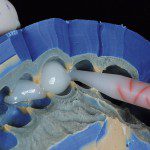

As imagens 18a, b, c e d apresentam o procedimento de moldagem com uma silicona de adição em etapa única. O material leve é injetado assim que o fio Pro-Retract 0000 é removido com o uso de uma pinça (figura 18a). O material leve, depois de injetado em todas as cervicais dentais, é aplicado um jato de ar para impelir o material contra os dentes (figura 18b); logo a seguir, é levada a moldeira em posição com o material pesado (Putty) (figura 18c). A vista final da moldagem, na qual se pode ver nitidamente que o material leve copiou adequadamente a região cervical dos dentes pode ser apreciada na figura 18d.

- Figura 18a

- Figura 18b

- Figura 18c

- Figura 18d